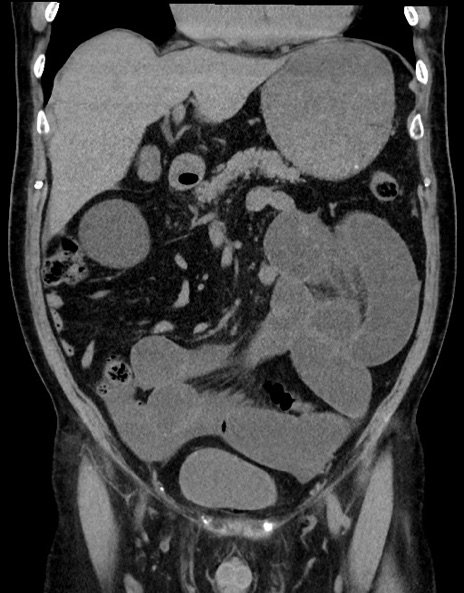

症例15(冠状断像)

【症例】70歳代男性

【主訴】腹痛

【現病歴】今朝から腹痛あり。全体的に痛い。特に左上の方。排ガスが今日はない。冷や汗が出る。

【既往歴】直腸癌術後

【身体所見】左側腹部〜上腹部に圧痛あり。腹膜刺激症状明らかなではない。軽度反跳痛。左下腹部に術後瘢痕あり。

【データ】WBC 7700、CRP 0.02